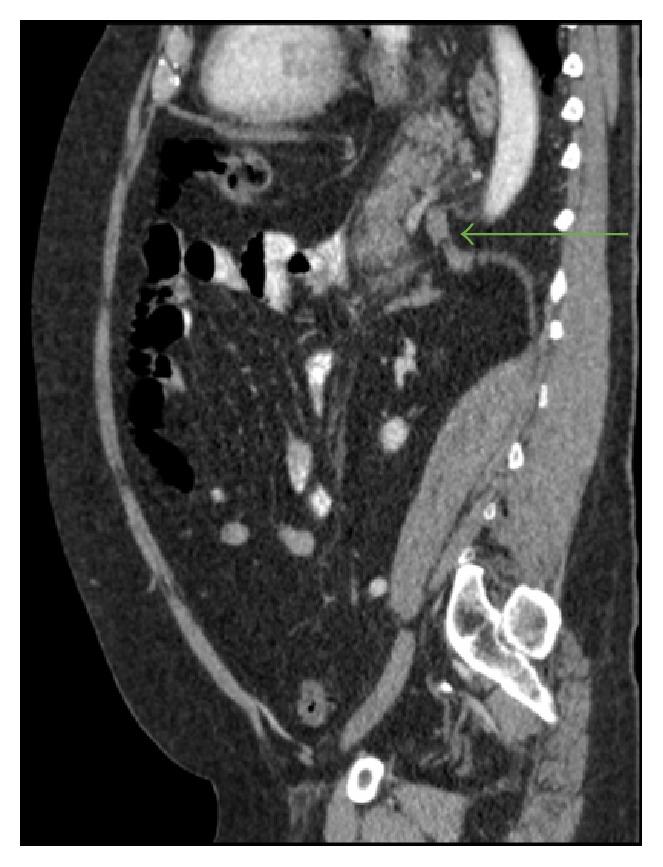

Hiatal hernia (HH) is the herniation of elements of the abdominal cavity through the esophageal hiatus of the diaphragm. A giant HH with pancreatic prolapse is very rare and its causing pancreatitis is an even more extraordinary condition. We describe a case of a 65-year-old man diagnosed with acute pancreatitis secondary to pancreatic herniation. In these cases, acute pancreatitis may be caused by the diaphragmatic crura impinging upon the pancreas and leading to repetitive trauma as it crosses the hernia; intermittent folding of the main pancreatic duct; ischemia associated with stretching at its vascular pedicle; or total pancreatic incarceration. Asymptomatic hernia may not require any treatment, while multiple studies have supported the recommendation of early elective repair as a safer route in symptomatic patients. In summary, though rare, pancreatic herniation should be considered as a cause of acute pancreatitis. A high index of suspicion for complications is warranted in cases like these.

食管裂孔疝(HH)是腹腔内容物通过膈肌食管裂孔的疝出。巨大食管裂孔疝合并胰腺脱垂非常罕见,其引发胰腺炎更是一种极为特殊的情况。我们描述了一例65岁男性患者,诊断为胰腺疝出继发急性胰腺炎。在这些病例中,急性胰腺炎可能由以下原因引起:膈肌脚压迫胰腺,当其穿过疝时导致反复创伤;主胰管间歇性折叠;与血管蒂拉伸相关的缺血;或胰腺完全嵌顿。无症状疝可能无需任何治疗,而多项研究支持对有症状患者早期择期修复是更安全的途径这一建议。总之,虽然罕见,但胰腺疝出应被视为急性胰腺炎的一个病因。对于此类病例,有必要对并发症保持高度怀疑指数。